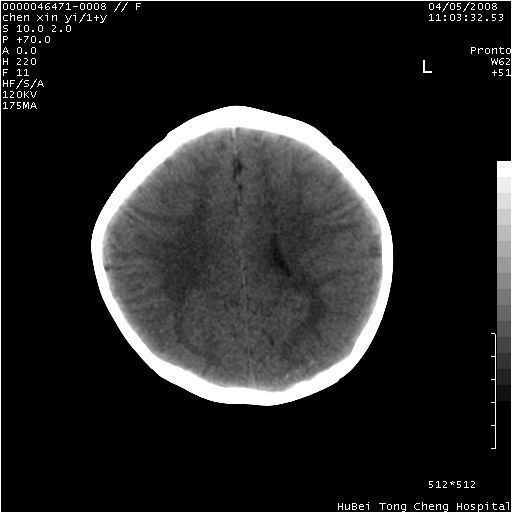

以下是引用zhangzhongshou在2008-4-9 12:54:00的发言:[br]请结合病史,有以下可能1、炎性肉芽肿钙化(含结核)2、寄生虫钙化(含脑囊虫)3、其他良性钙化性病变